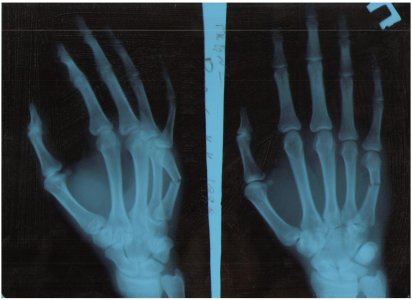

1 ноября сломал 5 пястную кость правой кисти.

В травмпункт обратился на следующий день. Первоначально мне наложили гипс с фиксацией мизинца и безымянного пальца и сказали прийти через 10 дней. Через 10 дней обнаружилось что кость сместилась и наложили повторно гипс. Через несколько дней сделали повторный снимок - на нем так же было видно смещение. Было решено отправить в стационар на операцию. В итоге операция была сделана 21 ноября. В кость была вставлена фиксирующая спица. В справке было написано спицу вынимать через 5-6 недель после контрольного снимка.